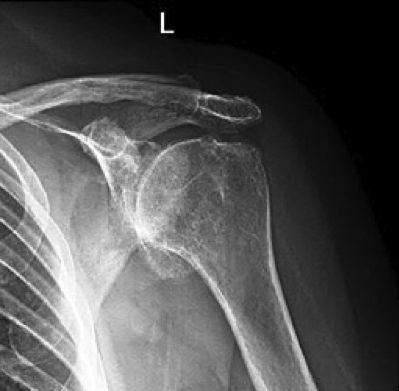

La articulación escapulohumeral es la que conecta la cabeza del húmero con la glena de la escápula, y es la articulación de la cintura escapular que mayor movimiento tiene, con desplazamiento en flexión y extensión del brazo, aproximación (aducción) y separación del mismo (abducción), rotaciones externa e interna, y movimientos combinados de antepulsión, retropulsión y circunducción. En esta articulación la artrosis se produce en la mayoría de los casos como consecuencia de traumatismos previos, inestabilidad o rigidez del hombro, artropatía por lesiones del manguito rotador, y osteonecrosis o enfermedades reumáticas que deforman la articulación.

Como consecuencia del desarrollo de artrosis escapulohumeral u omoartrosis, el paciente sufre dolor en el hombro y pérdida de movimiento del mismo. La cabeza humeral pierde su forma normal esférica y se va achatando, creciendo una corona osteofitaria en su periferia. Los tendones del hombro pueden estar afectados o no. Si el manguito rotador está roto la cabeza humeral asciende. La rotación externa está muy limitada y la abducción y antepulsión no suelen llegar a los 90º.